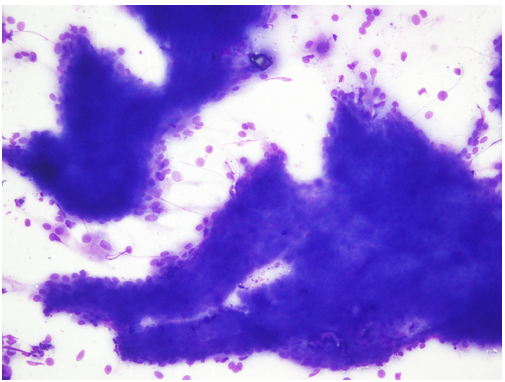

Fine needle aspiration (FNA) was performed with a 22-gaugeneedle attached to 20 mL syringe mounted on Cameco’ sholder. The aspirate consisted of 2 ml clear cystic fluid. Two smears were air-dried and stained with May-Gru?nwald Giemsa (MGG) and two wet-fixed and stained with Hematoxylin and Eosin (H&E). On microscopic examination, the smears showed tumor cells arranged in a prominent papillary pattern. The cells were small to medium and showed minimal nuclear pleomorphism with abundant cytoplasm (Figure 1).

Figure 1: Prominent papillary pattern, MGG [100x].

Focal areas of cells showingoncocytic change were also seen. Few mitotic figures could be appreciated.